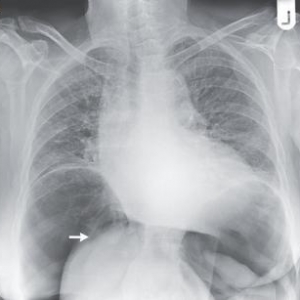

病例学习:气腹引起的肝旋转

2014年11月13日NEJM杂志临床影像栏目刊登了如下一则病例:患者,76岁女性,体健,因持续性直肠出血和腹痛做选择性结肠镜检查。检查过程因乙状结肠冗长而延迟,检查后,腹部突然膨胀并出现腹膜刺激征。站立位胸部平片 ...